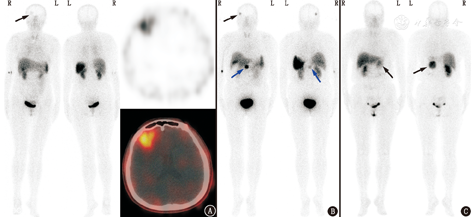

生长抑素受体显像对位于肾上腺外的副神经节瘤的诊断灵敏度很高(图3),文献报道68Ga标记生长抑素类似物显像对肾上腺外副神经节瘤诊断灵敏度可达100%[2,3],对肾上腺内副神经节瘤(嗜铬细胞瘤)诊断灵敏度<90%[2]。就诊断特异性而言,生长抑素受体显像阳性不等于就是神经内分泌肿瘤,很多类型的病变也可表达生长抑素受体2型,如脑膜瘤、肾癌、乳腺癌、淋巴瘤、肺癌、前列腺癌、头颈部肿瘤、肉瘤、甲状腺癌、星形细胞瘤、感染及炎性反应等[4,5],病例举例见图4。而关于本例需鉴别的其他2种疾病,近期有Castleman病生长抑素受体显像假阳性的报道[6,7],摄取程度与本例相似;虽然鲜见文献报道炎性肌纤维母细胞瘤的生长抑素受体显像情况,但炎性肌纤维母细胞瘤在病理上伴大量浆细胞和淋巴细胞浸润,而活化的淋巴细胞可有生长抑素受体高表达,理论上讲该病也有生长抑素受体显像假阳性的可能。